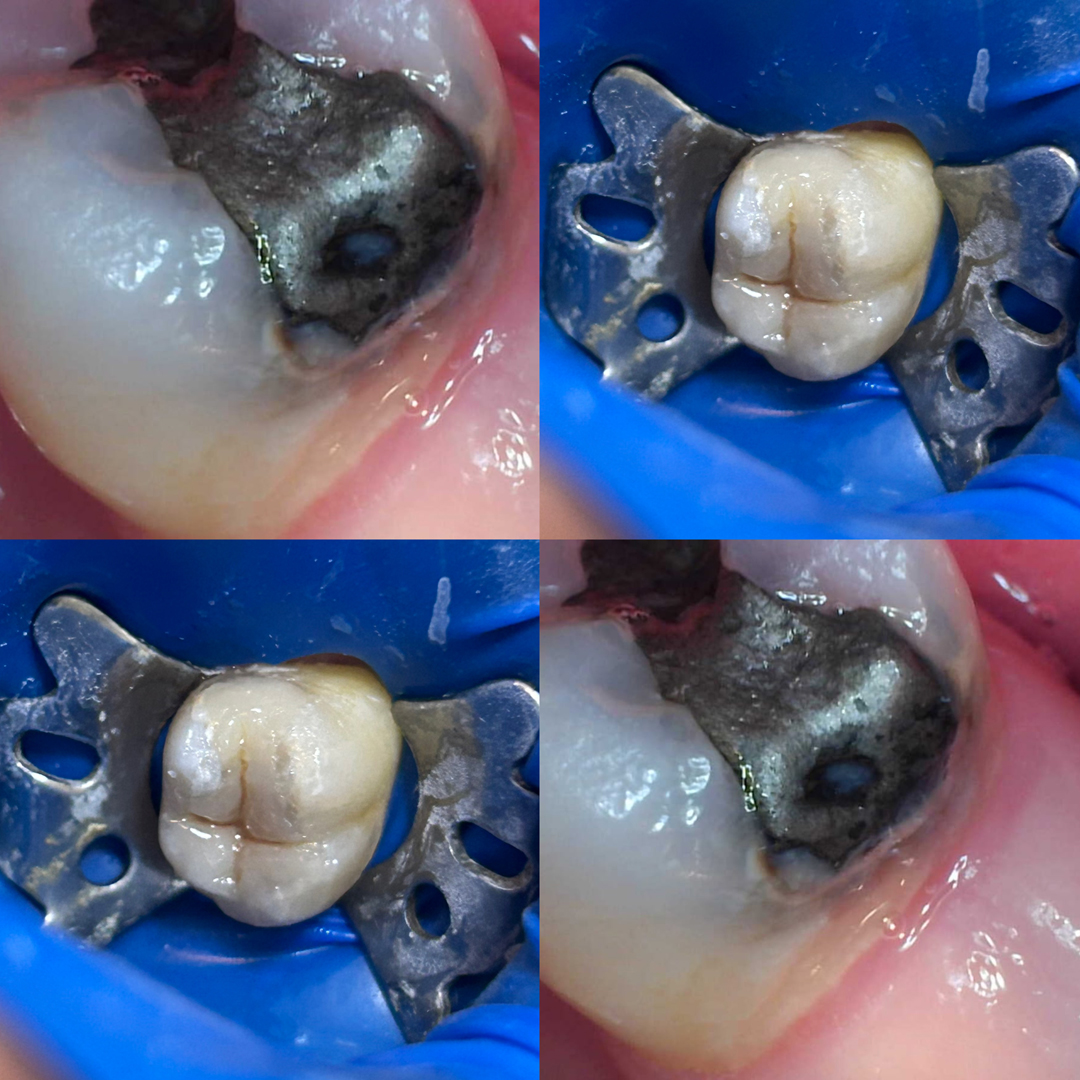

Restaurações mal adaptadas, dentes fraturados ou com cárie podem comprometer não só a estética, mas também a saúde bucal. Realizo tratamentos restauradores prezando pela longevidade, devolvendo função, saúde e estética.

Serviços Realizados:

● Restaurações estéticas em resina composta

● Tratamento de cáries

● Reparação de dentes fraturados

● Troca de Restauração